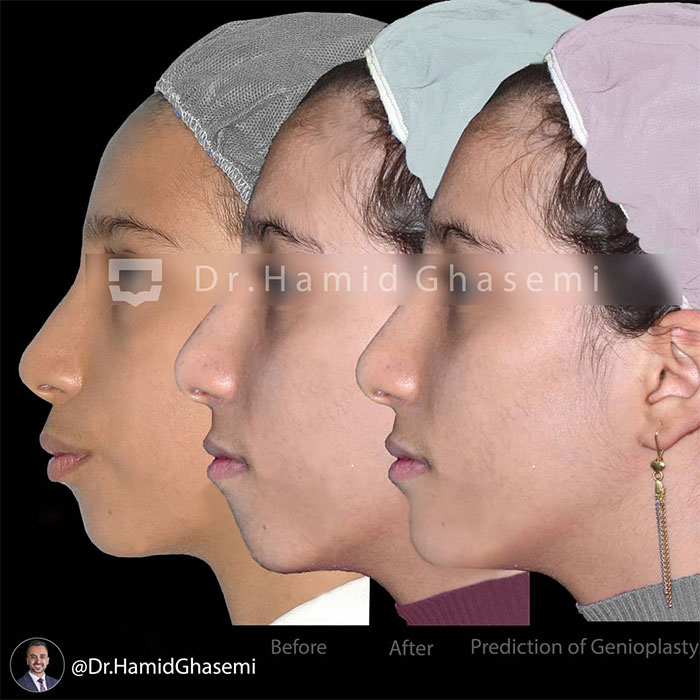

شماره پرونده : M 96_1144

توتال آرچ دیستالیزیشن دو فک در بیمار با جلوزدگی فک بالا و پایین.

Total arch distalization done for patient with bimaxillary dentoalveolar protrusion.